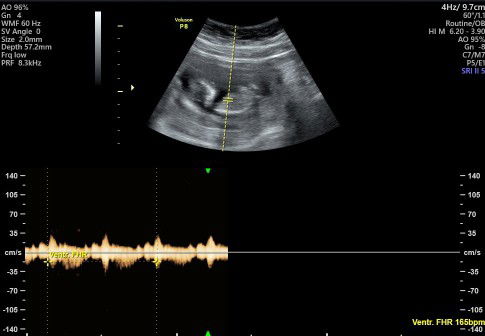

insya allh positif bun .. klo uda jelas coba lngsung usg aja